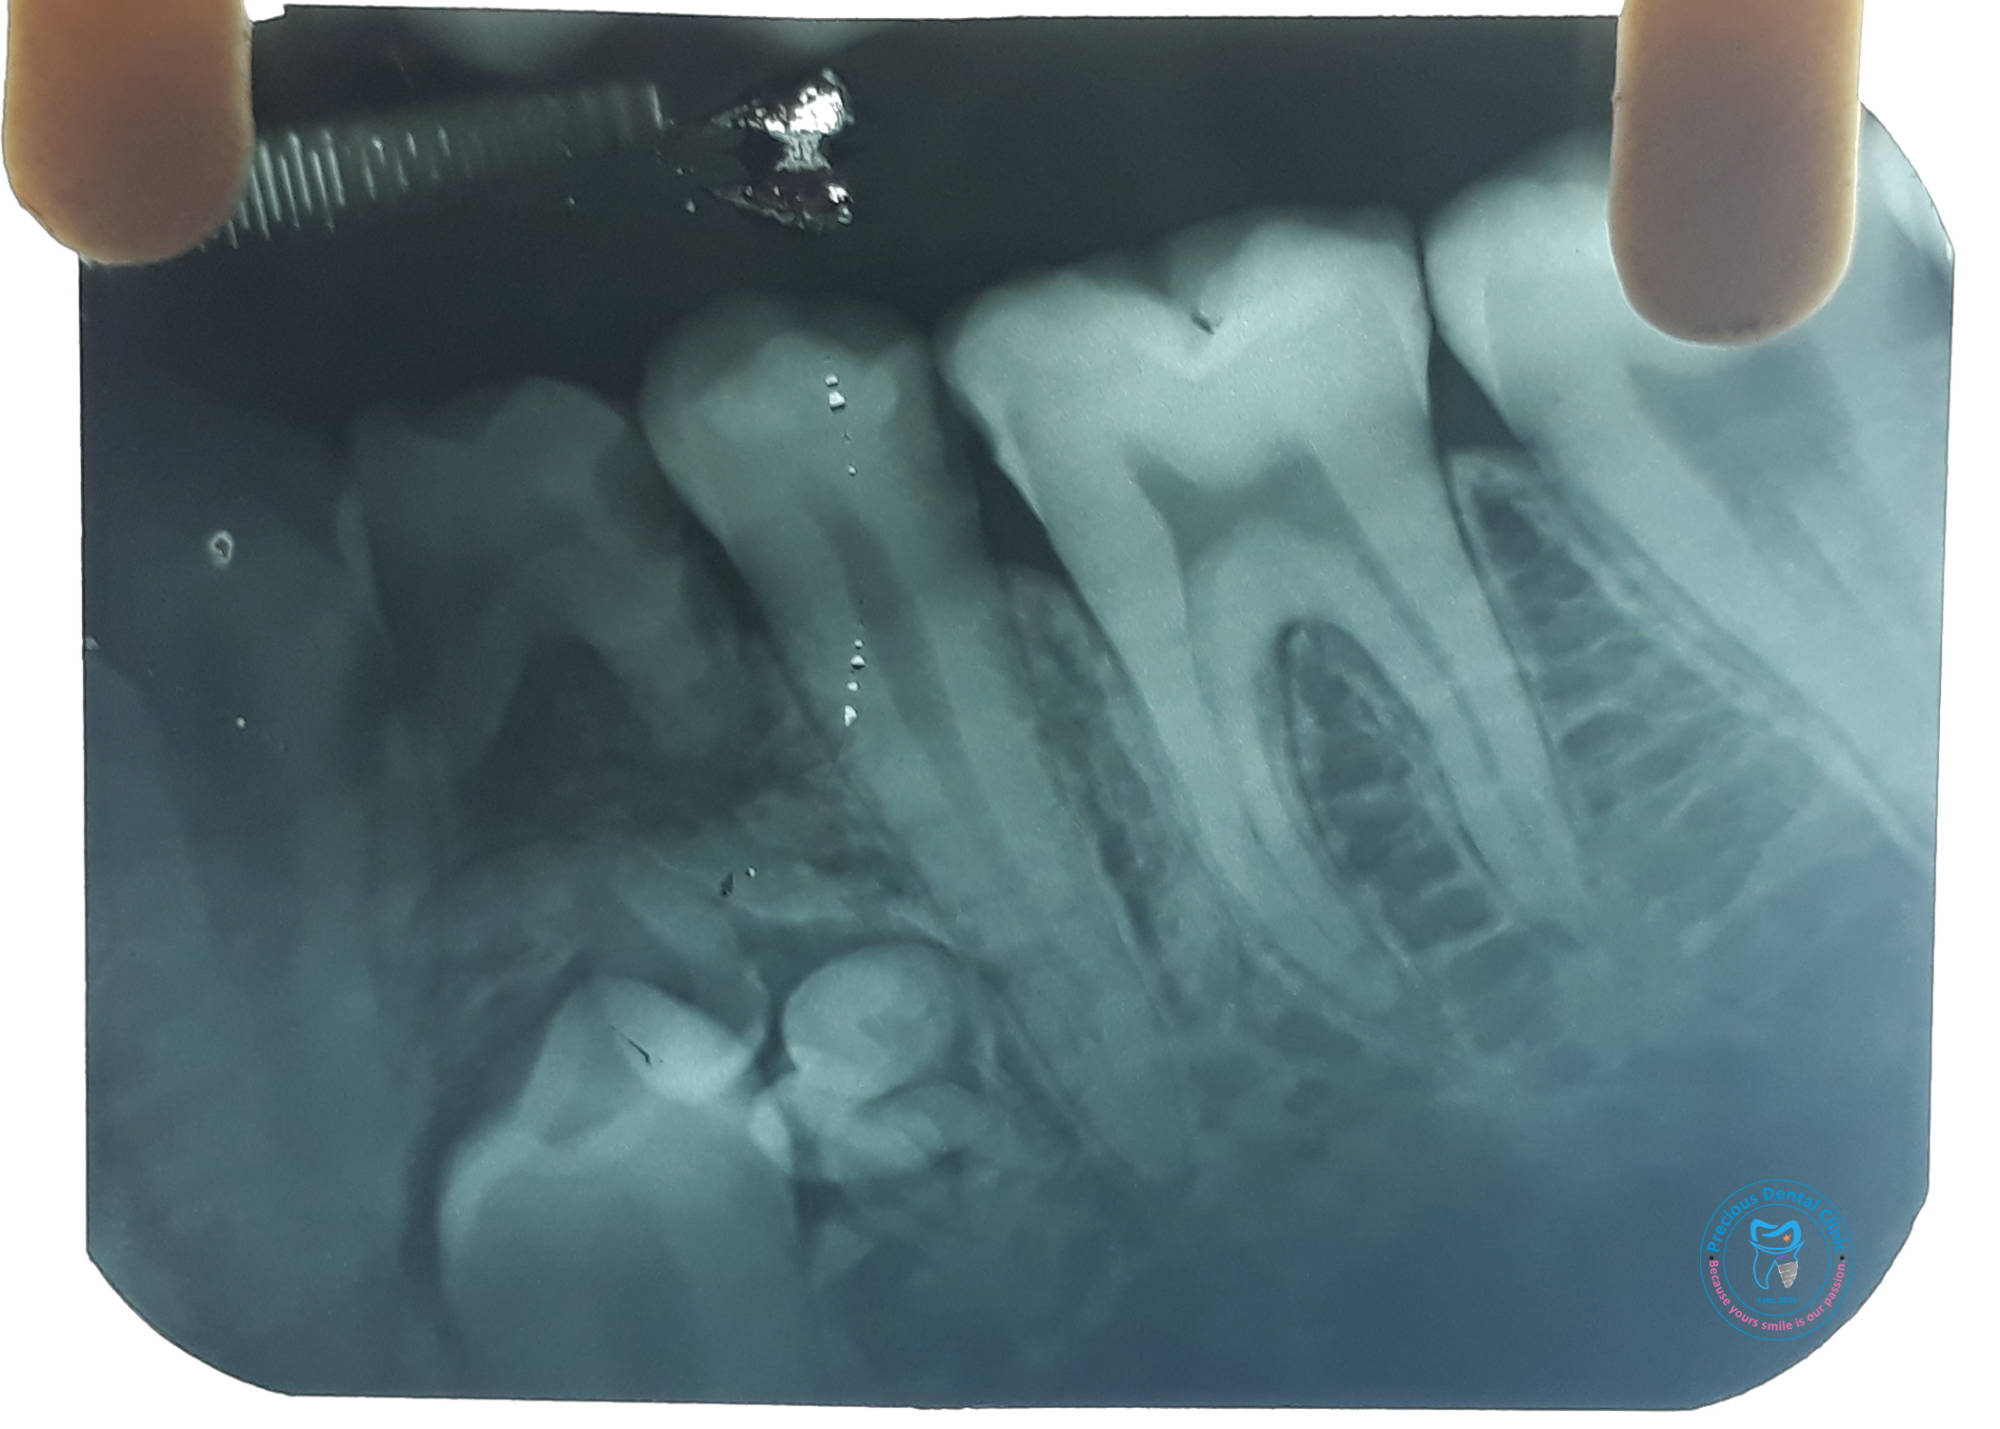

Supenumery Teeth Supenumery Tooth IOPAR

Supenumery Tooth IOPAR RTA